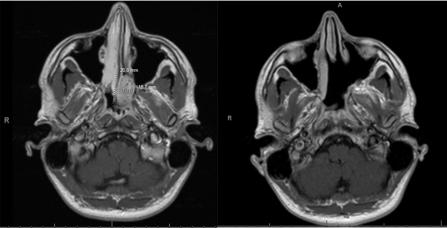

Image

MRI of a left olfactory neuroblastoma before and after resection

Magnetic resonance imaging (MRI) showing a left olfactory neuroblastoma with extension to the left medial orbital wall and the nasal septum before and after endoscopic surgery

Left olfactory neuroblastoma before and after endoscopic resection

A left olfactory neuroblastoma before and after endoscopic resection